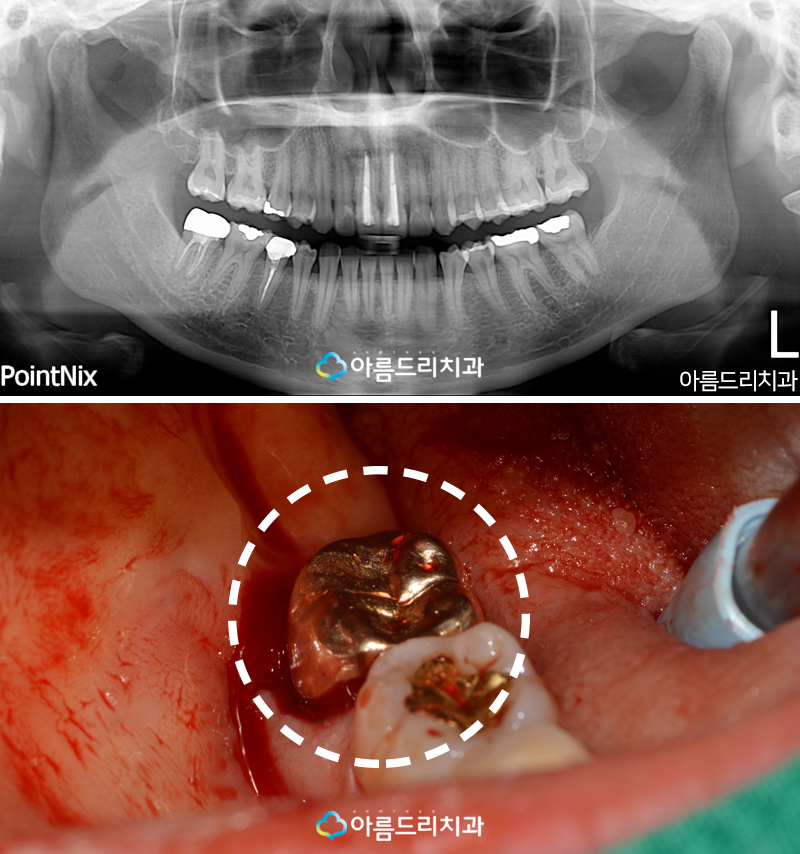

환자분께서는 30대의 여성 환자분이셨고 예전에 어금니에 문제가 있어 신경치료 후 골드 크라운 치료를 마친 분이셨습니다.

하지만 요 근래 어금니에 찌릿찌릿하고 참기 힘든 고통이 반복적으로 일어나 동네에 있는 치과에 갔더니 어금니를 발치하고 임플란트 를 해야한다는 청천벽력 같은 소식을 들었고 치아재식 후기 경험이 많은 아름드리치과에서 자연치아 살리기가 가능한지 문의해주셨어요.

환자분의 치아상태를 최첨단 3D디지털 장비 와 아름드리 파노라마 X-ray 사진으로 현재 어금니의 상태를 확인할 수 있었는데요.

우선 사진 상으로 확인해 볼때 뿌리 끝의 염증 이 확연하게 보이는 상태고 주변 잇몸의 상태 와 치조골 등의 상태는 괜찮아 보였습니다.

이론적으로만 하기에는 알아듣기 힘든 치료라 잇몸과 치아 사진을 통해 설명해 드릴께요.

치아재식술의 과정은 우선 치아의 뿌리에 있는 염증을 치료하기 위해 치아를 뽑고 치아의 뿌 리쪽 염증 부분을 제거하고 잇몸에 남아있는 염증을 치료한 후 15분 이내로 치료한 치아를 제자리로 식립후 고정하는 과정을 거칩니다.

아래의 사진을 보면 발치한 치아를 어떻게 치료하는지 대략적으로 감이 오실꺼에요.